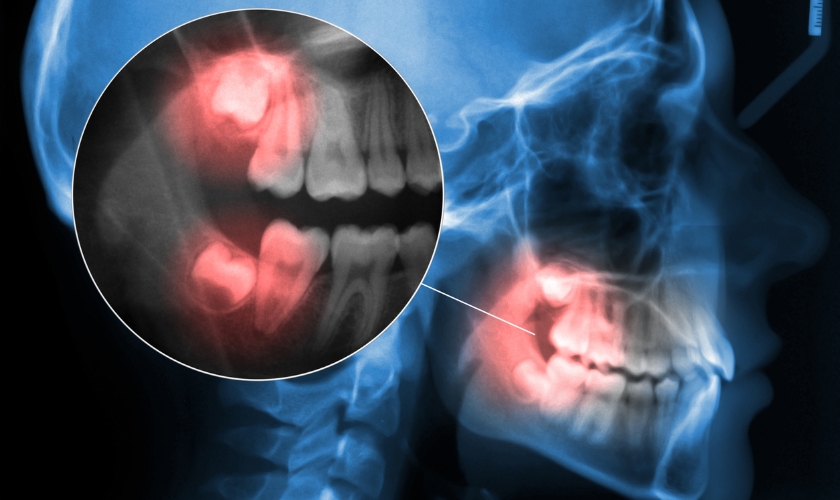

Wisdom teeth, or third molars, are the last set of teeth to emerge, usually between the ages of 17 and 25. Due to changes in human diets and jaw sizes over time, there often isn’t enough space for these teeth to grow properly. Most people have four wisdom teeth—two on the top and two on the bottom—but not everyone has adequate room in their mouth for these additional teeth, which can lead to issues like impaction, crowding, and infection.

- Impaction: When third molars don’t have enough room to emerge properly, they can become impacted, growing sideways or partially erupting. Impacted third molars can cause pain, swelling, and infection.

The best way to determine the best course of action for your third molars is to consult with a dentist. They will examine your mouth, take X-rays, and discuss your options with you.